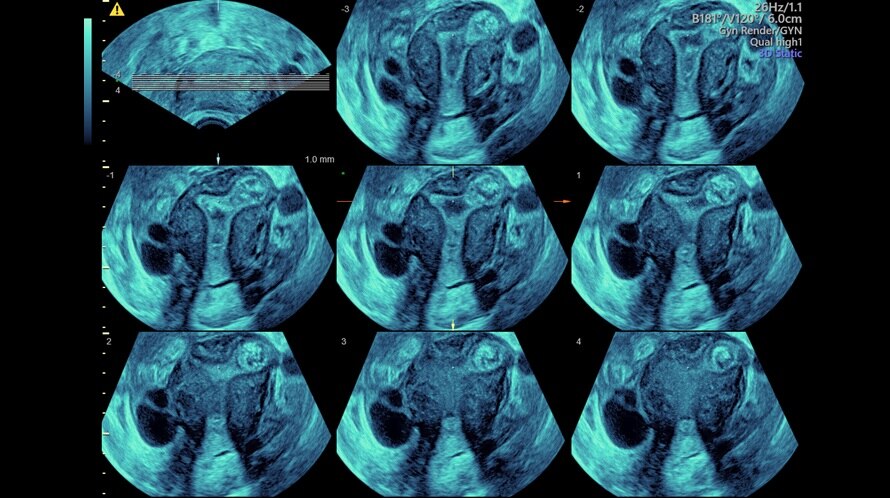

Voluson Expert 22 nasce come sistema specialistico puro, sviluppato intorno alle esigenze reali di ostetricia e ginecologia:

Architettura Radiance ottimizzata per imaging volumetrico

Sistema progettato esclusivamente per applicazioni OB/GYN

Massima coerenza dell’immagine anche in condizioni cliniche complesse

Rendering 3D/4D ad alta fedeltà

Valutazioni ginecologiche di precisione

Imaging volumetrico per follow-up e consulenze multidisciplinari